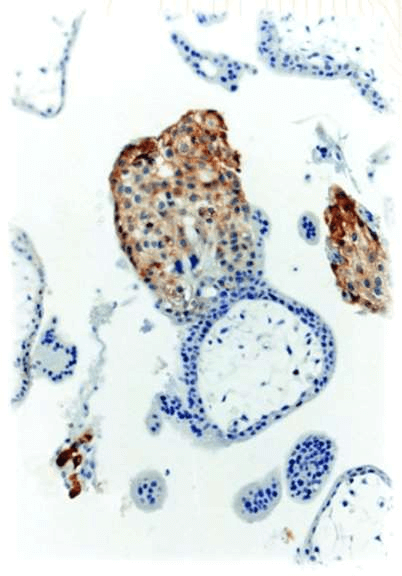

Fig.4 IHC: HLA-G clone (MEM-G/1)